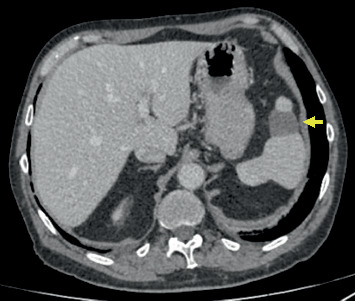

简介:不同组织学类型的黑色素瘤同时发生是一种罕见的事件,报道的发病率为0.2%至8.6%。病例报告:我们提出一个病例的病人诊断为阶段IIB结节性黑色素瘤和阶段IIIC上皮样细胞黑色素瘤在3个月内。手术切除两个病变后,在闭孔区观察到淋巴结肿大,表明转移扩散。因此,开始了纳武单抗和伊匹单抗联合免疫治疗。Nivolumab和ipilimumab的剂量分别为1和3mg /kg,每3周给药,共4次。此后,继续使用纳武单抗单独治疗,剂量为每2周3mg /kg。患者接受了三个周期的免疫治疗,最初联合静脉注射甲基强的松龙,后来过渡到口服地塞米松方案。患者最初表现出良好的临床反应,无不良反应。然而,在第三次输注后,出现了严重的腹泻,导致每日液体损失超过8l并伴有低钾血症。因此,甲基强的松龙被静脉注射(2mg /kg/天)。此外,患者经历了脾梗死,自发性消退,没有导致脾功能不全。在最近的随访评估中,未发现淋巴结肿大,每隔3个月继续进行监测。讨论:虽然罕见,但同时出现在不同解剖部位的黑色素瘤强调了提高患者警惕和全面临床监测的必要性,以促进早期发现和及时干预。结论:及时启动靶向免疫治疗可改善患者预后和转归。

Introduction: The synchronous occurrence of melanomas of varying histological types is an uncommon event, with reported incidences ranging from 0.2% to 8.6%. Case Report: We present the case of a patient diagnosed with Stage IIB nodular melanoma and Stage IIIC epithelioid cell melanoma within a 3-month period. After surgical excision of both lesions, lymph node enlargement was observed in the obturator region, indicating metastatic spread. As a result, combined immunotherapy with nivolumab and ipilimumab was initiated. Nivolumab and ipilimumab were administered at doses of 1 and 3 mg/kg, respectively, every 3 weeks for a total of four doses. Thereafter, treatment was continued with nivolumab alone at a dose of 3 mg/kg every 2 weeks. The patient underwent three cycles of immunotherapy, initially combined with intravenous methylprednisolone, later transitioned to an oral regimen with dexamethasone. The patient initially demonstrated a favorable clinical response without adverse effects. However, after the third infusion, severe diarrhea developed, leading to daily fluid losses exceeding 8 L and associated hypokalemia. Therefore, methylprednisolone was administered intravenously (2 mg/kg/day). Additionally, the patient experienced a splenic infarction that resolved spontaneously without resulting in asplenia. At the most recent follow-up evaluation, no lymph node enlargement was detected, and surveillance continues at 3-month intervals. Discussion: Although rare, the simultaneous emergence of melanomas at distinct anatomical sites underscores the necessity for increased patient vigilance and comprehensive clinical monitoring to facilitate early detection and timely intervention. Conclusion: Prompt initiation of targeted immunotherapy may improve patient prognosis and outcomes.